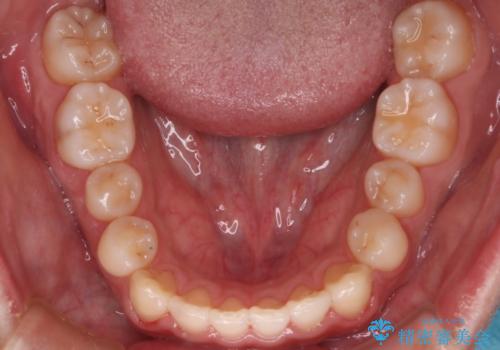

- 前歯のがたつきを主訴に来院されました。初診時、右上2番の口蓋側転位と右下7番の舌側傾斜が認められました。

インビザラインにてIPRと歯列弓拡大を行い、ゴム掛けで噛み合わせを改善する治療計画を立てました。

マウスピースの使用時間が短いため、シュミレーション通り進むか不安でしたが

治療期間1年で、主訴である前歯のがたつきを改善出来、

奥歯の噛み合わせも良くなりました。